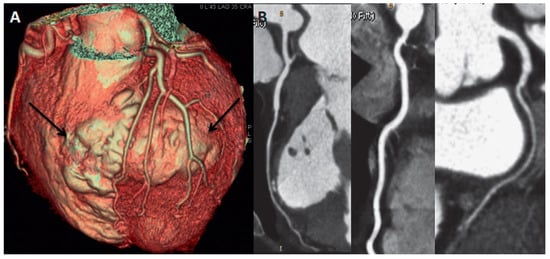

Echocardiography showed the presence of a large LV antero-lateral wall aneurysm (maximal dimensions of 57 × 41 mm) with the wall thinning resulting in the moderately depressed LV ejection fraction of 35% with preserved contractility of the remaining LV segments (Figure 1A,B, arrows). Coronary artery disease with previous silent myocardial infarction was suspected. Subsequently performed coronary angiography demonstrated normal coronary arteries.

Figure 1. Echocardiography parasternal short-axis (A) and apical two-chamber view (B) showing the presence of large left ventricular antero-lateral wall aneurysm (arrows).